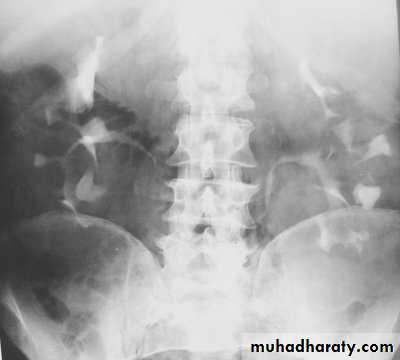

IVU

Large kidney .

Lobulated out-line.

Distortion of pelvi- calyceal system depend on cyst size, number and position.

In advanced cases there is elongation and stretching of minor and major calyces ( spider leg).

In advanced cases IVU shows non-functioning kidney .